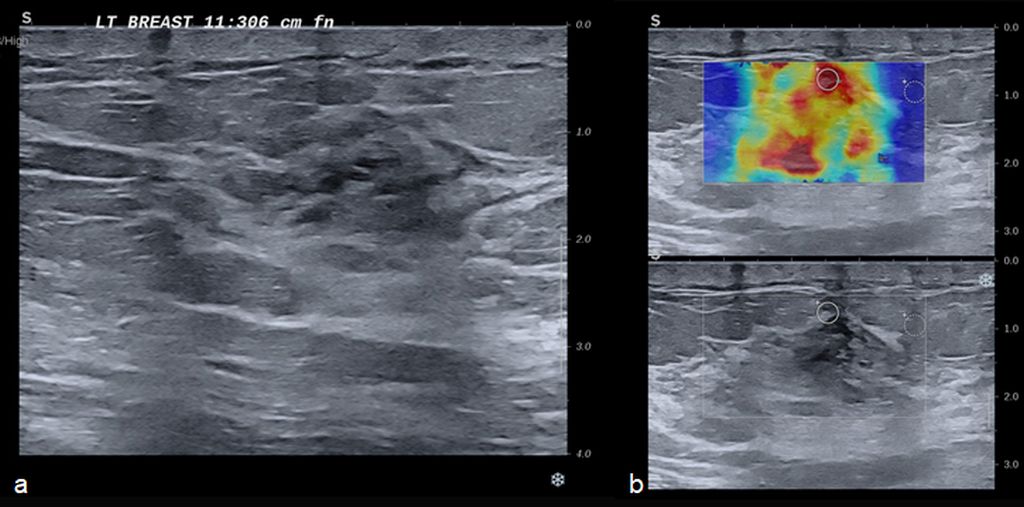

Low energy 2D mammogram images of both breasts in CC and MLO views (figure 1) demonstrate focal asymmetry with architectural distortion in the upper central quadrant of the middle third in the left breast with associated architectural distortion. Fine pleomorphic calcifications in regional distribution are noted in the inner central and upper inner quadrants of the left breast (figure 2). Diffuse skin and trabecular thickening is noted in the left breast. On post contrast recombined images (Figure 3), the area of focal asymmetry shows a heterogeneously enhancing mass with washout on delayed image (MLO). Heterogeneous and clumped non-mass enhancement in diffuse distribution is noted involving the areas of calcifications in the inner quadrant (red circle in figure 4) which could represent calcified ductal carcinoma in situ (DCIS) as well in the outer quadrant (green circle in figure 4) which could represent non-calcified DCIS. To differentiate between non-mass enhancement in diffuse distribution and background parenchymal enhancement, comparison with the opposite breast should be done. In our case there is minimal background parenchymal enhancement in the right breast (figure 3a and 3c) whereas clumped enhancement in diffuse distribution in the left breast (figure 3b and 3d) suggestive of non-mass enhancement in the left breast. Ultrasound correlation revealed an irregular isoechoic mass with indistinct margins with no posterior features measuring 2.2x1.9x1.6cm at 11:30 O'clock position, 6cm fn in left breast. It is hard on elastography (Figure 5). Non-mass ductal abnormalities in the form of irregular prominent and dilated ducts filled with soft tissue and echogenic foci within are noted in upper inner, lower inner and upper outer quadrants of left breast (Figure 6). The whole abnormality extends from the 8-12-3 o'clock position of the left breast. On tomo slices two equal density lesions with indistinct margins are noted in the upper outer quadrant of the right breast. On post contrast recombined images, they show heterogeneous enhancement. Ultrasound correlation revealed two hypoechoic lesions with circumscribed margins in the upper outer quadrant. Multiple enlarged left level I and level II lymph nodes are noted, which show asymmetrical cortical thickening and loss of fatty hilum (figure 7). MRI post contrast subtraction axial images (figure 8a and b) revealed a lesion with irregular shape and margins in the upper central quadrant of left breast with associated non-mass enhancement in diffuse distribution in upper inner, upper outer and lower inner quadrants confirming the mammographic extent of abnormalities (figure 8c).